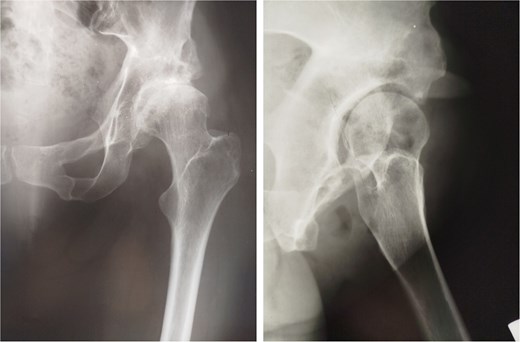

In 1984, a 35-year-old female patient presented to our department with severe left groin pain. Preoperative pelvic radiographs revealed acetabular dysplasia with subluxation at Crowe Grade I and Tönnis Grade I. A Pol Le Cœur corrective TPO was performed (Fig. 1). Over the following 28 years, radiographic examinations demonstrated progressive articular degradation despite the initial clinical success of the osteotomy.

Postoperative anteroposterior radiographs of the pelvis, showing Pol Le Cœeur triple pelvic osteotomy performed on a 35-year-old female patient to treat an acetabular dysplasia in the left hip, at Grade 1 Crowe’s classification.